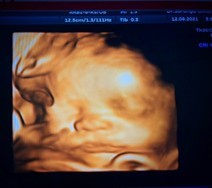

ฮัลโล่~.อบอุ่นดีที่ในท้อง🛌